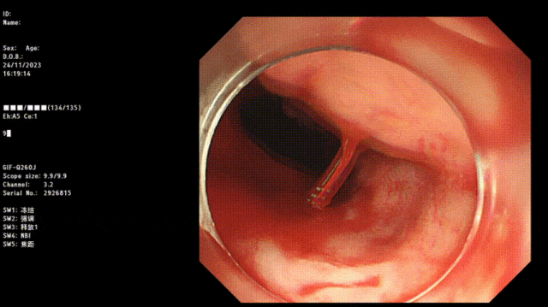

1. 内镜检查:包括胃镜、结肠镜等内镜检查技术,可以直接观察到消化道黏膜的情况,帮助医生确定出血的原因。

止血成功